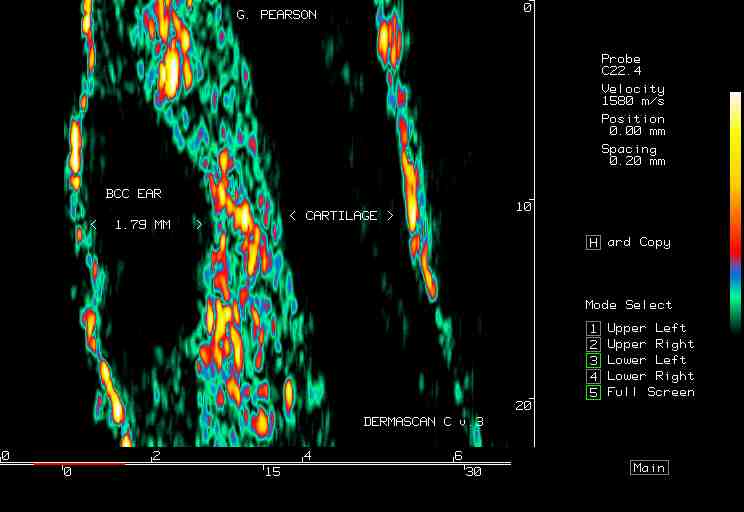

| Tumors |  BCC on the ear |

BCC, various sites |